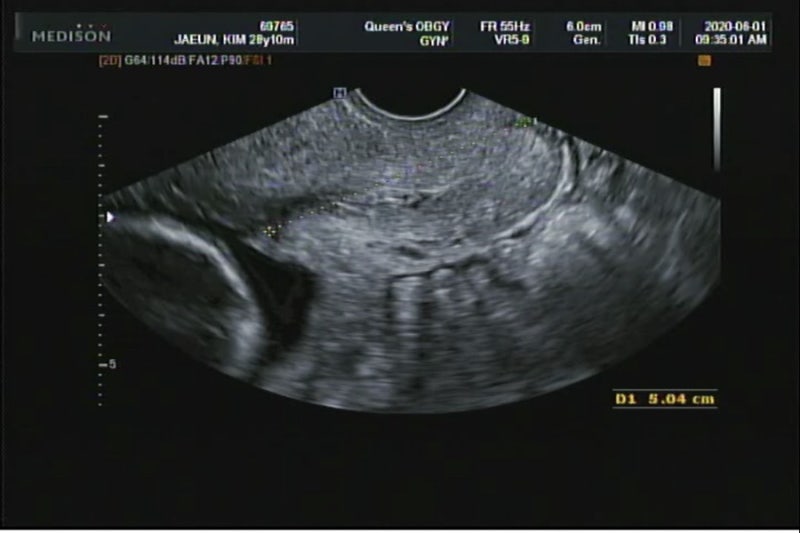

임신 19주차 주요 진료내용은 자궁경부장 확인과 태반 위치 확인! 당연히 아기 크기도 확인~자궁경부 길이와 태반 위치는 질 초음파로 하고 아기 확인은 배초음파로 확인.즉… 초음파 2회 확인!

저는 열심히 재고 수치는 알려주지 않고, 들어보니 4cm 이상으로 길다고, (저희 담당 선생님은 이상이 있다는 것만 말씀해주시는.. 경향이… 아무 말도 해야 정상…(웃음) 태반의 위치가 조금 아래이긴 하지만 모양과 위치가 앞으로 올라가지 않을 것 같다고 합니다.그래서 앞으로 진료 때 지켜보도록 할게!